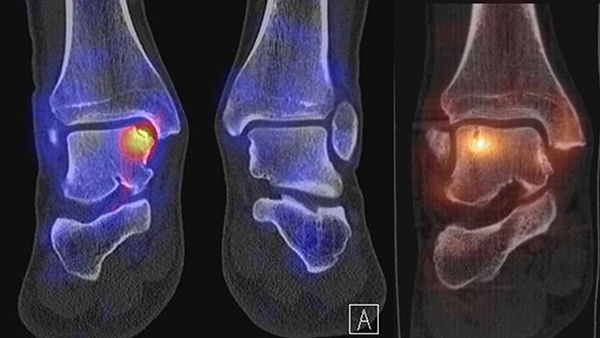

In Abbildung 3.4. ist ein typisches Beispiel für ein symptomatisches Os trigonum dargestellt.

Zum Lesen der Bildbeschreibung und zur Vollansicht bitte das Bild anklicken. Bild: H. C. Rischke